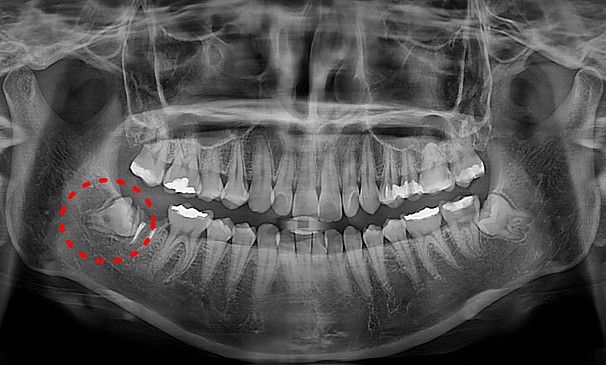

자가치아이식술

박OO님 전후사진 | 치료 기간 : 1주

치료 전